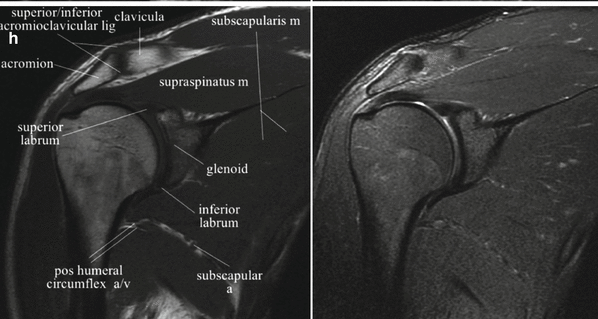

자기공명영상(MRI)은 초전도 자석, 고주파, 컴퓨터 등을 이용해 인체 조직과 혈관을 2차원 또는 3차원으로 검사하는 방법이다. 기기의 특성상 테스트 시 큰 소음이 나는 것 외에는 테스트에 따른 통증이나 부작용이 거의 없습니다. 검사가 시작되면 신체가 실린더 안으로 들어가고 신체가 느낄 수 없는 특정 무선 주파수가 검사 영역으로 전송됩니다. 수신된 정보를 컴퓨터로 처리하여 인체의 모든 부분을 단면 및 입체영상으로 재구성하여 질병의 유무를 진단하는 검사입니다. 검사를 받기 어려우신 분* 심장박동기 시술을 받으신 분* 동맥류 협착증이 있으신 분 * 신경자극기를 시술받은 분 * 인공와우 시술을 받으신 분 * 폐소공포증 환자 진찰 전 확인이 필요한 분 * 머리, 심장, 뼈에 금속 보형물을 이식한 적이 있거나 몸에 금속 파편이 있는 사람 임신 중인 경우 검사 가능성에 대해 의사와 상의하세요.* 임신 중이거나 임신 가능성이 있는 사람이 있습니다. 검사의 장점과 상대적 위험성을 고려하여 담당 의사와 상담 후 결정하시는 것이 좋습니다.* 보청기, 틀니, 머리핀, 벨트, 시계, 열쇠, 지갑, 카드, 귀금속류 등 금속류 물품을 소지한 경우 휴대폰은 검사에 방해가 될 수 있으므로 별도로 챙겨가시기 바랍니다. 안전한 곳에 보관해야 하며, 카드가 지워지거나 시계, 휴대폰 등이 파손될 수 있습니다. 단, 고정된 인공치아나 보철물은 허용됩니다.* 검사 전 금식이 필요한 성인 및 소아 복부(간, 신장, 췌장 등) (단, 산부인과 골반검사의 경우 3시간 정도 소변을 참는 것이 도움이 됩니다.) 시간.) 절차는 어떻게 진행되나요? .* 필요한 경우 진정제를 투여할 수 있으며, 검사 종류에 따라 조영제를 투여할 수 있습니다.* MRI 검사대를 기계에 삽입한 후 원통형 구조물(스캐너) 내부에서 영상화가 시작됩니다. 구조물 내부에서 이루어지기 때문에 다소 답답한 느낌이 들 수 있습니다. 테스트가 시작되면 몇 분 간격으로 소리가 들려오며, 평소처럼 차분한 마음으로 가만히 누워 있을 수 있습니다. 숨을 참고 숨을 내쉴 수 있습니다. 검사 후에는 무엇을 해야 합니까?* 검사 후에는 식사를 해도 됩니다. 드물게 조영제 사용 후 조영제에 대한 과민증이 발생할 수 있습니다. 과민반응에는 경미한 구토, 두드러기, 얼굴이 붉어지는 현상, 기침, 쉰 목소리, 콧물, 반점, 일시적인 호흡 곤란 등이 포함됩니다. 증상은 일반적으로 별다른 조치 없이 사라집니다. 출처 서울대학교병원

광주어깨. CPM재활한방병원 무릎수술 후 수정> MRI 스캔으로 이를 보완하는 것이 무엇인지 살펴보겠습니다. 광고 후 계속됩니다. 다음 주제 작성자 취소 광주허리통증 치료 좋은한의원 재생 0 좋아요 0 좋아요 공유 0:00:00 재생 음소거 00:00 00:00 실시간 설정 전체화면 해상도 currentTrack 비활성화 자막 재생 속도 NaNx 해상도 자막 설정 비활성화 옵션 텍스트 크기 배경색 재생률 0.5x 1.0x(기본값) 1.5x 2.0x 알 수 없는 오류가 발생했습니다. 도움말이 음소거되었습니다. 도움말 라이센스 이 영상은 고화질로 재생할 수 있습니다. 설정에서 해상도를 변경해보세요. 자세히 보기 0:00:00 접기/펼치기 IDD 광주감압치료병원 허리통증 치료 잘하는 광주한방병원 제2절 회사가 보상하는 항목 총액의 80%에 해당하는 금액(실제로 지급한 금액을 말한다) 본인)의 ‘항목별 공제금액’에서 규정한 의료급여의